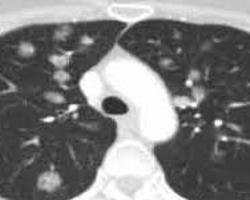

肺假性淋巴瘤(pulmonary pseudolymphoma,PL)又称结节性淋巴组织样增生(nodular lymphoid hyperplasia),系指肺内局部淋巴组织增生性疾病,通常呈单个结节,且限于单个肺叶内。